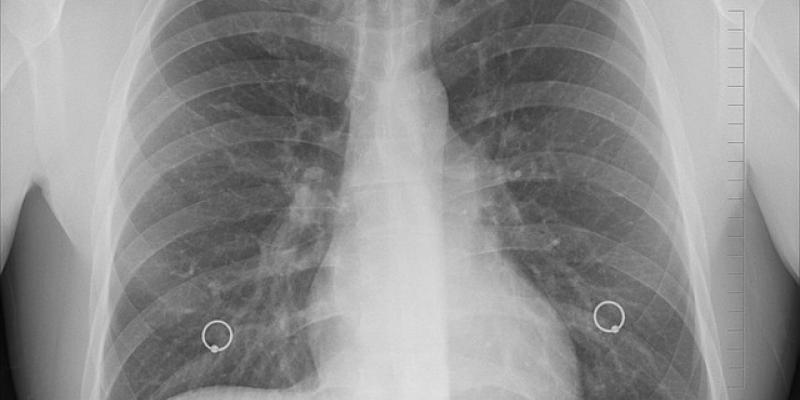

El cáncer de pulmón microcítico, de células pequeñas, es un subtipo de cáncer de pulmón muy agresivo, asociado al consumo de tabaco, que representa entre un 15 y 20 por ciento de los casos.